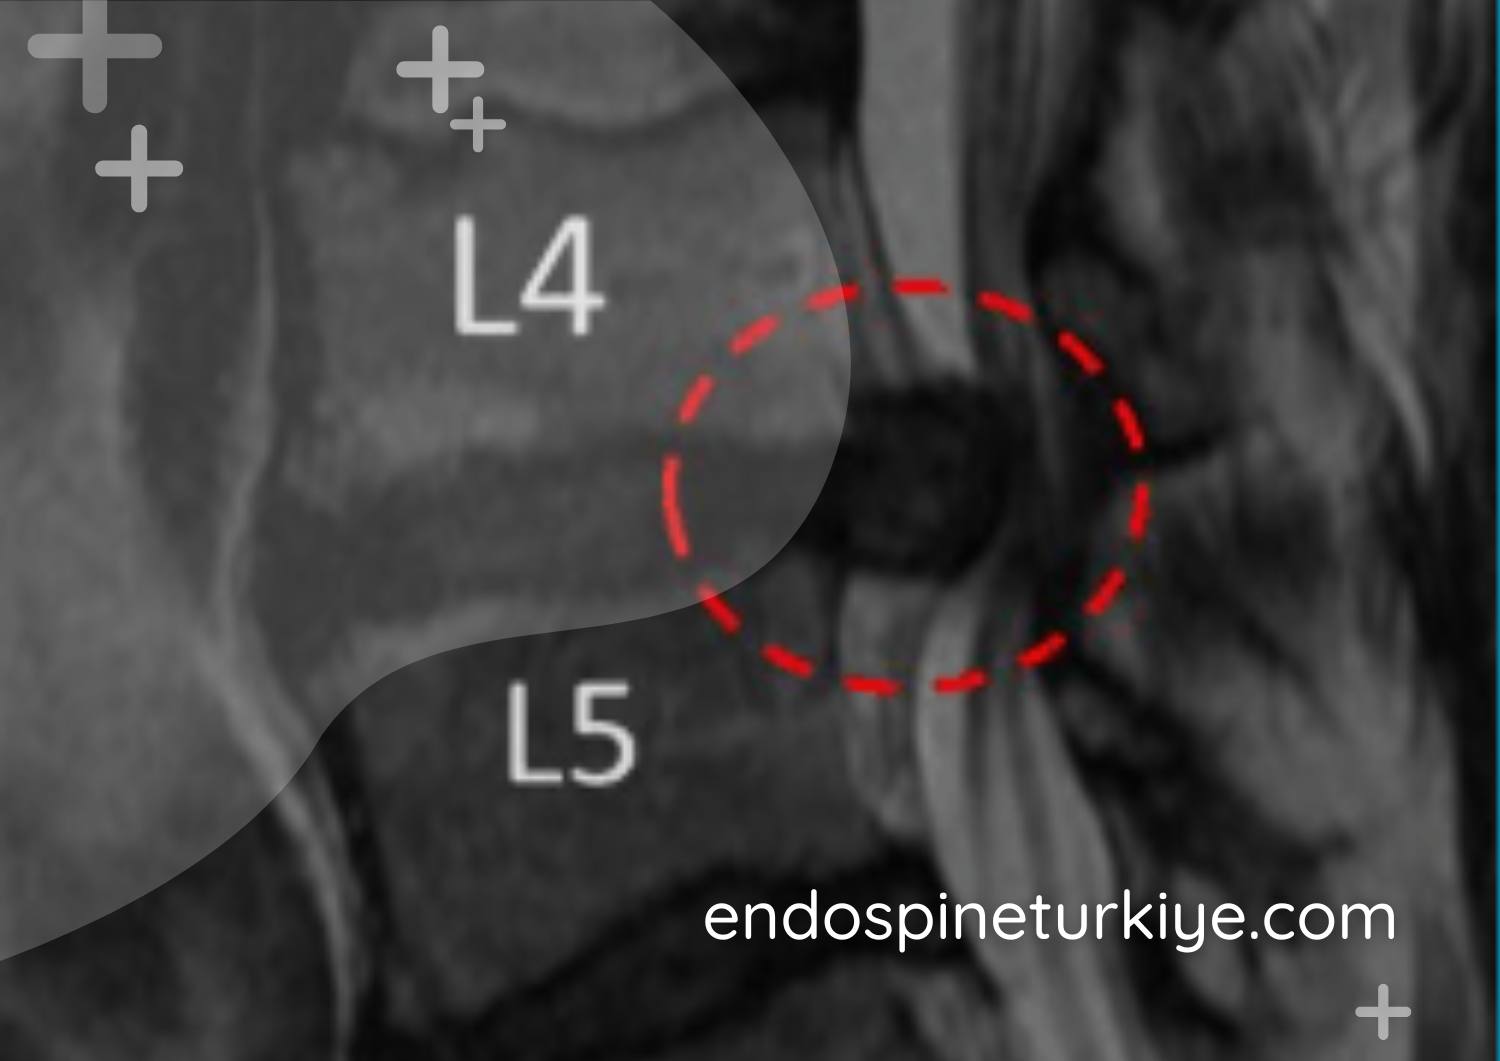

Kanal daralması ameliyatı sonrası - Genişletilmiş omurga kanalı

Tedavi Sonrası

Genişletilmiş kanal